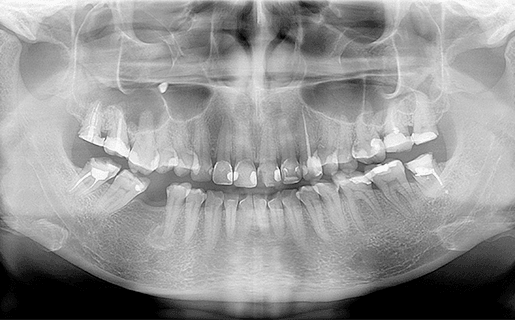

歯科ドックとは、レントゲン検査や歯周検査以外に唾液検査、口臭検査、位相差顕微鏡による細菌検査、

CTによるさらに詳細な画像診査などによって、現在の口腔内の状況を綿密に診断し科学的に評価することを目的としています。

三次元の高画質画像を用いることで、断層方式パノラマX線写真や口内法X線撮影法では判別できない、痛みや症状の原因の究明に役立ちます。

歯科用CT による撮影を行います。

当院のCTは、次世代CT再構成診断ソフト「GIDORA」を搭載しておりますので、これにより、精度の高い3D画像を構築していきます。この画像検査により得られる情報を基に、診査・診断および治療を行っていきます。